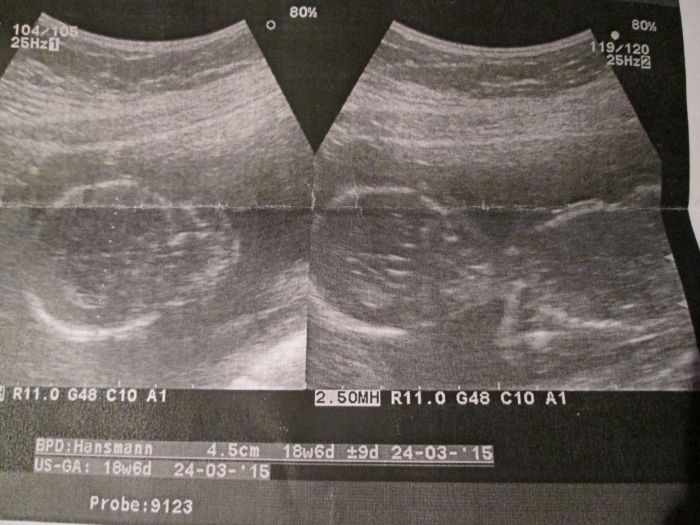

Ahoj holky. Tak včera jsem byla na velkým ultrazvuku a screeningu . Srdíčko nám bije dobře. Ledviny v pořádku. Močový měchýř se naplňuje. Všechno je zatím v pořádku. Koukala jsem jak se mi hýbe v bříšku. Občas cítím pohyby . Přikládám sem dvě fotečky. Už mám postýlku objednanou a kočárek už máme taky vyhlídnutý.